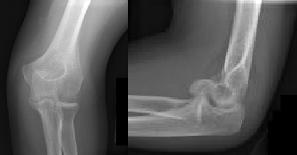

Figures 1 and 2 are the radiographs of a 35-year-old man who has elbow pain after falling from a ladder onto an outstretched hand. Examination reveals elbow pain, swelling, limited motion, and normal neurologic function.

A pathognomonic radiographic feature of this injury is a